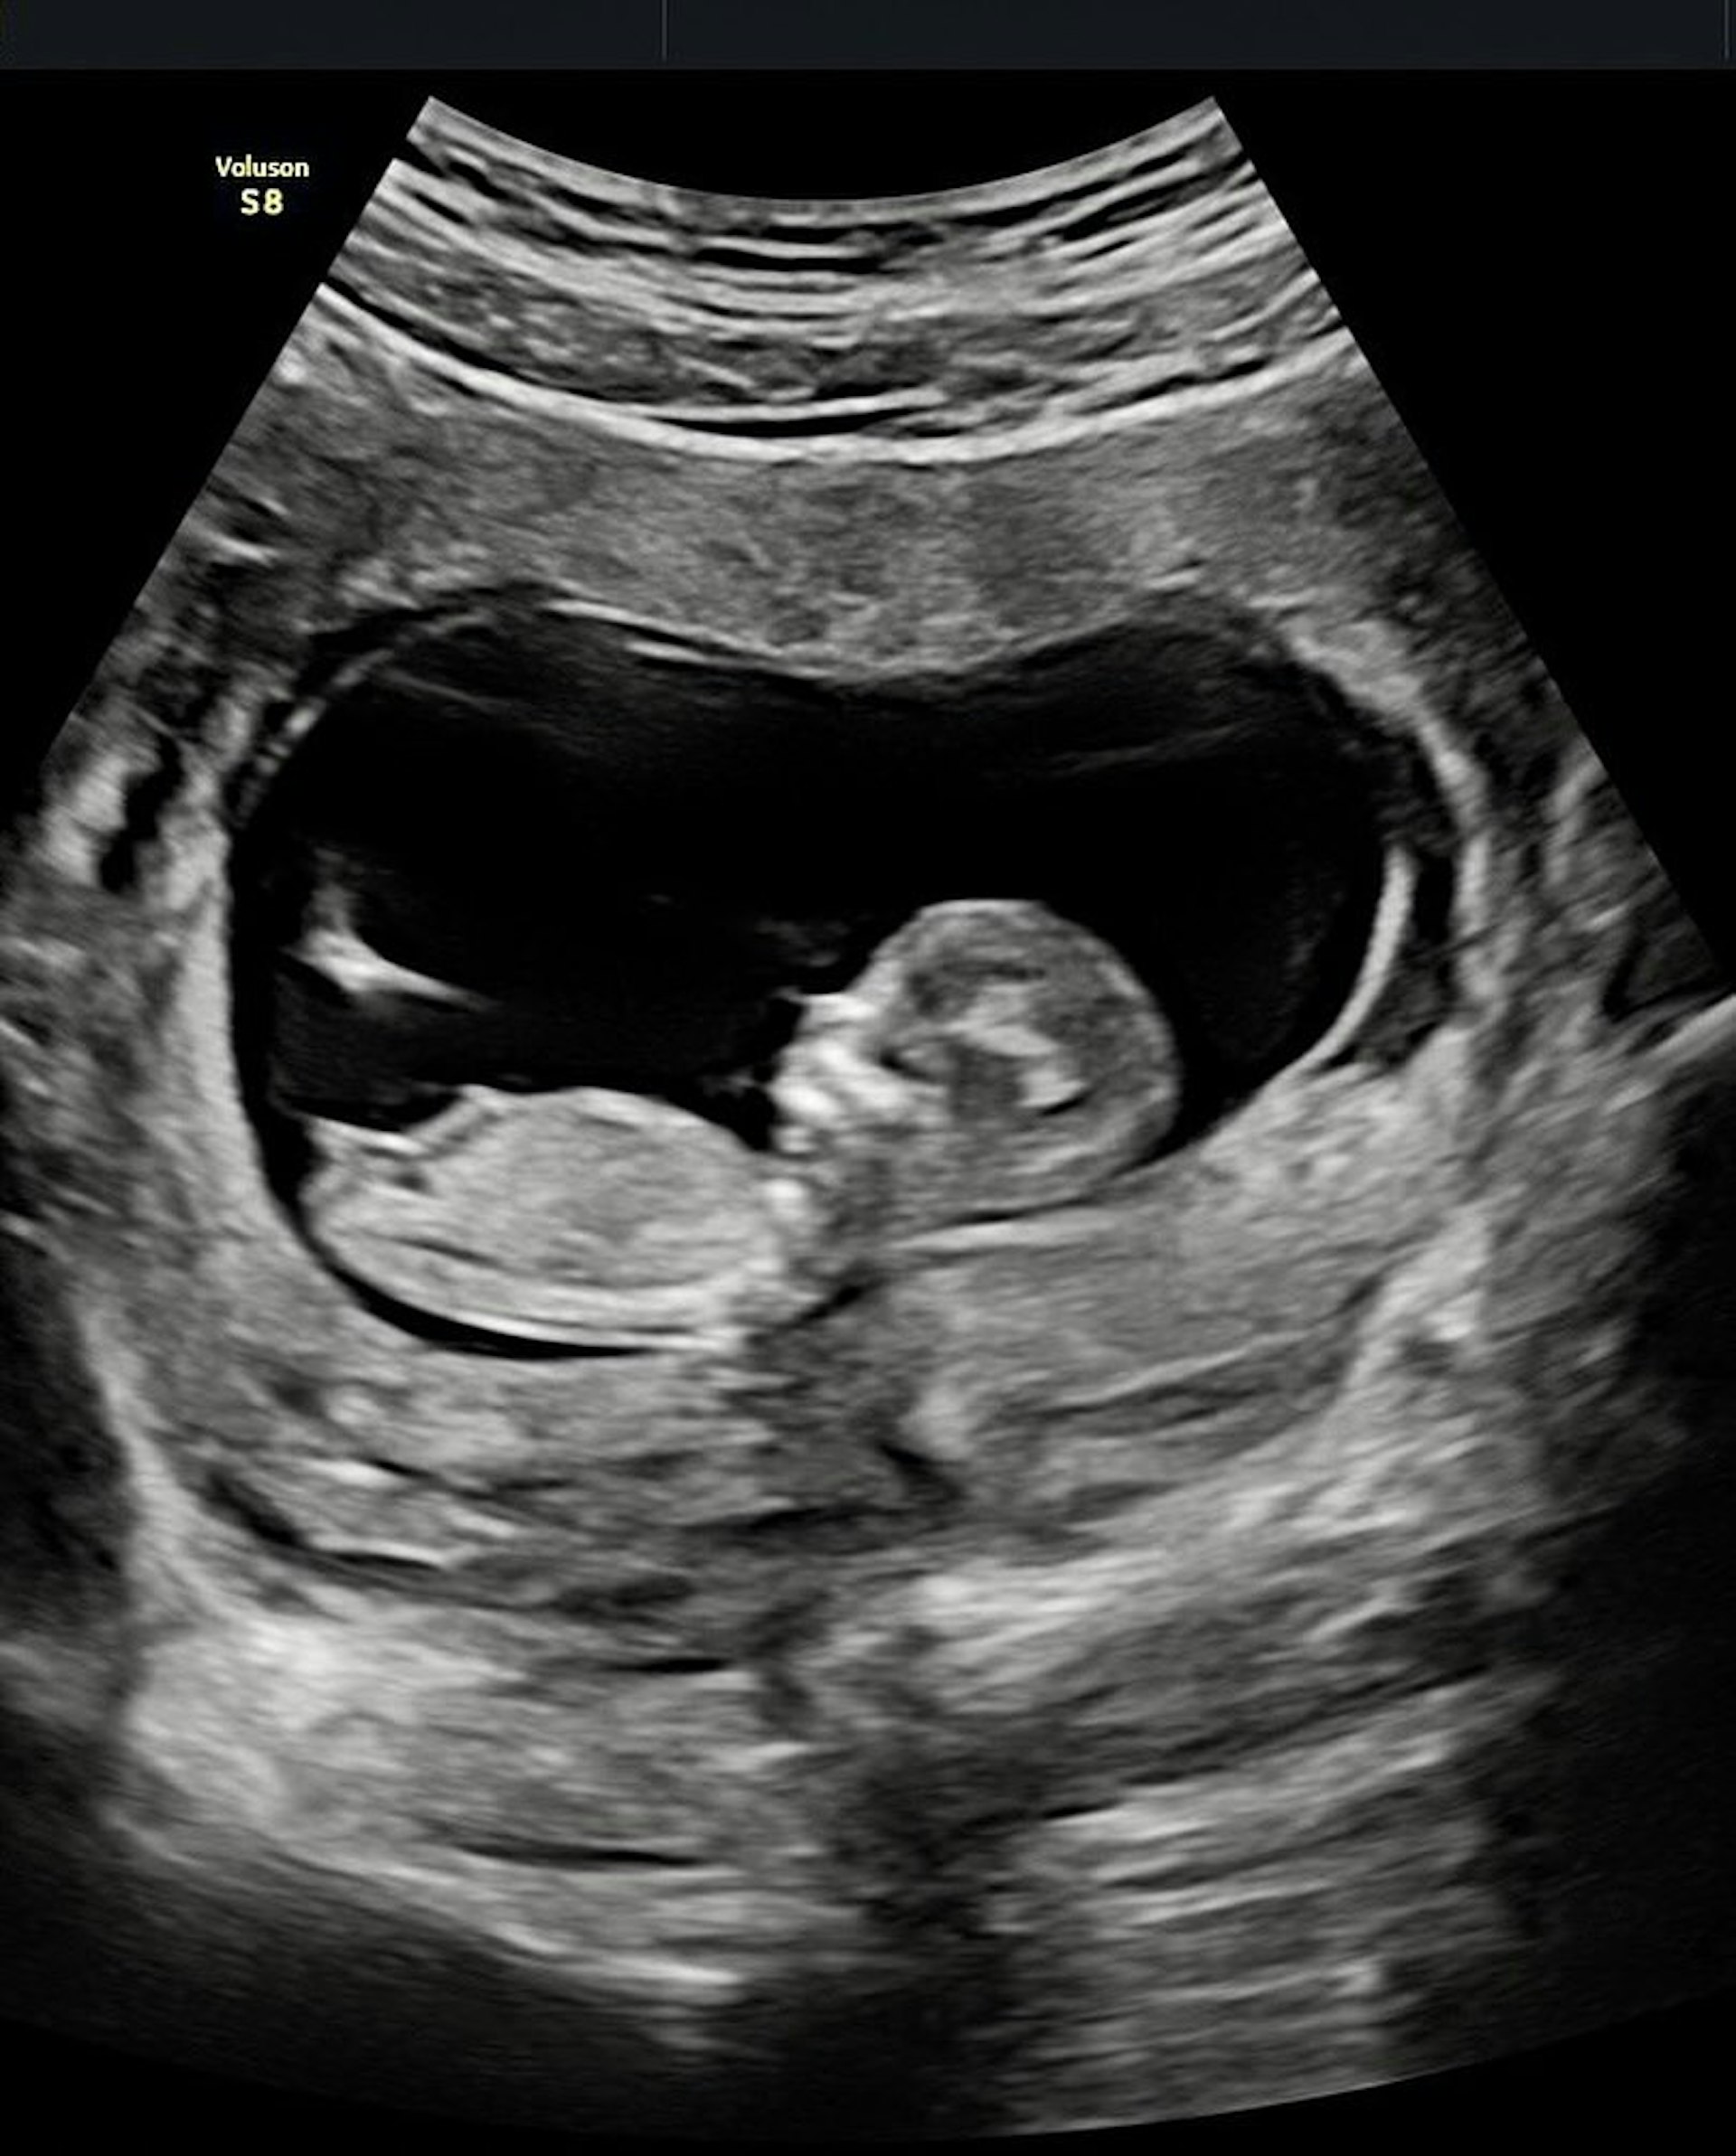

有「醫界王陽明」之稱的台灣醫生賴弘國,也是阿嬌的前夫,他在2020年5月與阿嬌離婚後,曾一度傷心欲絕聲稱被阿嬌毀了人生,難以再婚,但他與阿嬌離婚不到兩年,於2022年初便與Alice奉子成婚,同年8月老婆生下兒子,現時兒子已經1歲多,昨晚他在社交平台上載一張照聲波照,並寫道:「感恩的心,歡迎龍寶」,宣布太太再次懷孕,兩年抱兩,可喜可賀。